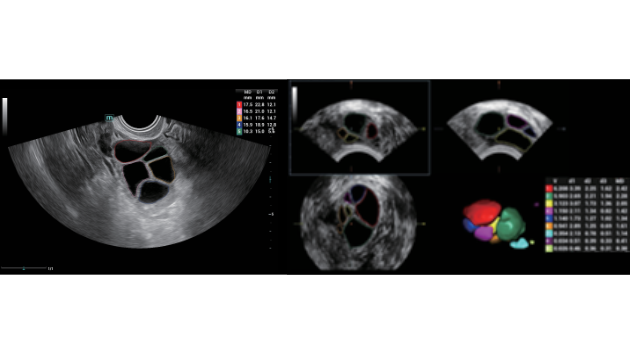

Indipendentemente dalle attività svolte in ospedale o in clinica, oppure se si desidera affinare le proprie capacità nella diagnostica per immagini generale negli ambiti della salute della donna o cardiovascolare, questa serie di soluzioni fornirà potenti strumenti per essere sempre un passo avanti.

Soluzioni di diagnostica per immagini complete con tecnologia ZST+

La piattaforma ZST+ è un'innovazione straordinaria, che rappresenta un'evoluzione nel campo dell'ecografia. Grazie alla trasformazione delle metriche a ultrasuoni dal beamforming convenzionale all'elaborazione basata sui dati di canale, supera la tradizionale limitazione del trade-off tra risoluzione spaziale, risoluzione temporale e uniformità dei tessuti, offrendo una qualità d'immagine eccezionale per infinite soluzioni di imaging con miglioramenti continui.